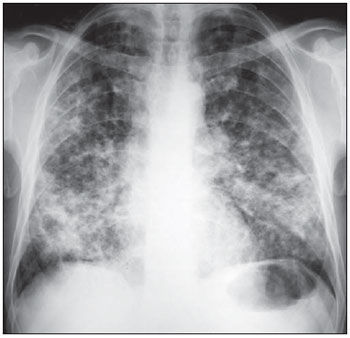

Identificação: LF, 67 anos, masculino, casado, pintor de carros aposentado, procedente de Sobradinho-DF. Queixa Principal: Tosse, falta de ar e febre há 2 dias. HDA: Tosse com expectoração esbranquiçada há dois anos, com piora progressiva. O quadro acompanhava-se de falta de ar aos esforços e chiado no peito esporádico. Em seguimento ambulatorial com diagnóstico espirométrico de DPOC, fazia uso irregular da medicação e não cessou o tabagismo. Há seis meses refere piora da tosse, que se tornou mais persistente e com pouca expectoração mucosa. Relata piora da tosse, com expectoração amarelada e febre não aferida há 2 dias. Antecedentes pessoais: Refere HAS, dislipidemia e cardiopatia. Nega DM e passado de TB; Antecedentes familiares: Pai falecido por IAM aos 50 anos, mãe e irmãos vivos e hígidos; Medicações em uso: anlodipino 10 mg/dia, AAS 100 mg/dia e sinvastatina 20 mg/dia. Hábitos de vida: Tabagista de 50 anos/maço; ex-etilista de fermentados aos finais de semana. Exame físico:Bom estado geral, desperto, orientado, corado, dispneico, acianótico, anictérico, febril. FC=82 bpm, PA=120x70 mmHg, Tax=38,6 ºC, FR=26 irpm, SatO2 86% em ar ambiente. Ritmo cardíaco regular em dois tempos, bulhas hipofonéticas Tórax com aumento do diâmetro antero-posterior, murmúrio vesicular diminuído e presença de raros sibilos. Crepitações grossas difusas, crepitações finas em base esquerda. Abdome normotenso, indolor, sem visceromegalias palpáveis, ruídos hidroaéreos presentes. Extremidades com pulsos periféricos presentes e simétricos, sem edemas. Gasometria arterial: pH 7,30 PaO2 56 mmHg SatO2 85% em ar ambiente PaCO2 52 mmHg HCO3 26mEq/L AG: 20 BE -4. Laboratório: Hematócrito: 47,5% Hemoglobina: 15,6g/dL Leucometria: 15700 (10% bastões) Plaquetas: 280.000 Creatinina: 1,5 mg/dL Potássio: 4,2 mEq/L Sódio: 138 mEq/L Glicemia: 94 mg/dL Conduta inicial: Iniciado O2 suplementar pormáscara de Venturi 30%, 15L/min. Nebulização com 10 gotas de berotec e 20 de atrovent. Hidrocortisona 200 mg, endovenosa. Colhidas hemoculturas e escarro para gram e cultura. Persistiu com sintomas inalterados após as medidas iniciais. A baciloscopia de escarro e o PCR para BK foram negativos. A melhor opção antibiótica inicial, dentre as abaixo é:

Answer

• Ampicilina + sulbactan

• Clindamicina + Ceftriaxona

• Piperacilina + tazobactan + azitromicina

• Cefepime